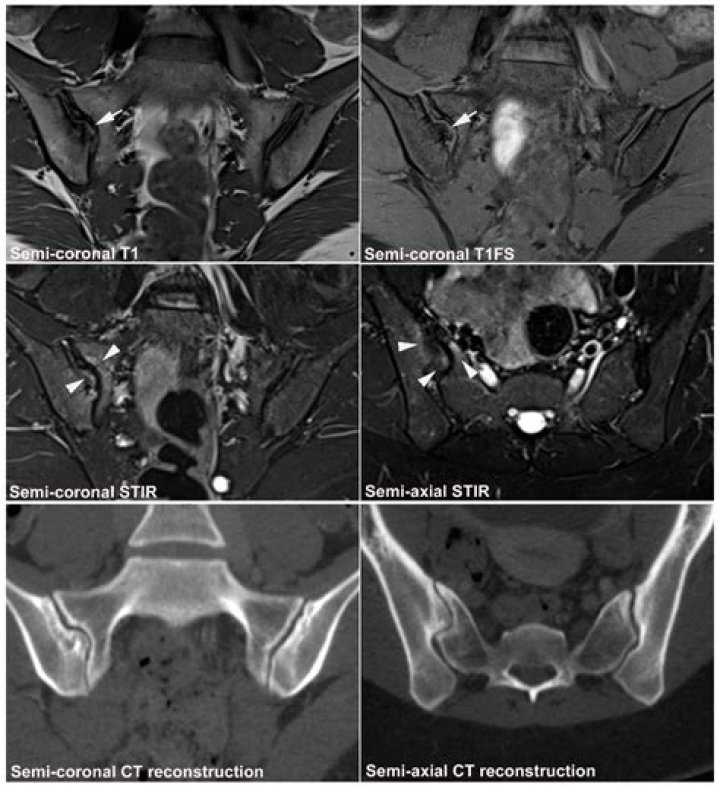

In chronic injuries, MRI may be useful in demonstrating scar tissue formation at the site of injury and involving important anatomic locations of muscles, as well as focal or diffuse fat atrophy of muscles affected, which may correlate with persistent clinical symptoms and loss of function.